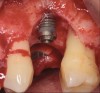

Following a similar paradigm of treating peri-implantitis the same way that periodontitis is regularly successfully treated, based on the mechanical removal of biofilms adhered to implant/abutment surfaces, different protocols of nonsurgical implant debridement using different mechanical, physical, and chemical mechanisms have been evaluated (Figure 12 through Figure 15). In general, the use of different protocols combining treatments aimed to decontaminate the implant surface (eg, mechanical, lasers) and control the infection process (eg, antiseptics, antibiotics) have shown clinical and significant improvements in the commonly used surrogate outcomes (mean reductions in PPD of around 1.2 mm and mean reductions in the scores of BOP of about 50%) but have not resulted in disease resolution18 or a high degree of predictablility.19 There is currently no specific nonsurgical therapy that has shown efficacy in the resolution of peri-implantitis, and the clinical improvements reported in the clinical studies were not sufficient for the arrest of the disease, leaving the standard of care in the treatment of peri-implantitis as surgical in most cases.20

Fig 15. Access flaps to allow mechanical debridement of implant surfaces.

Figure 15